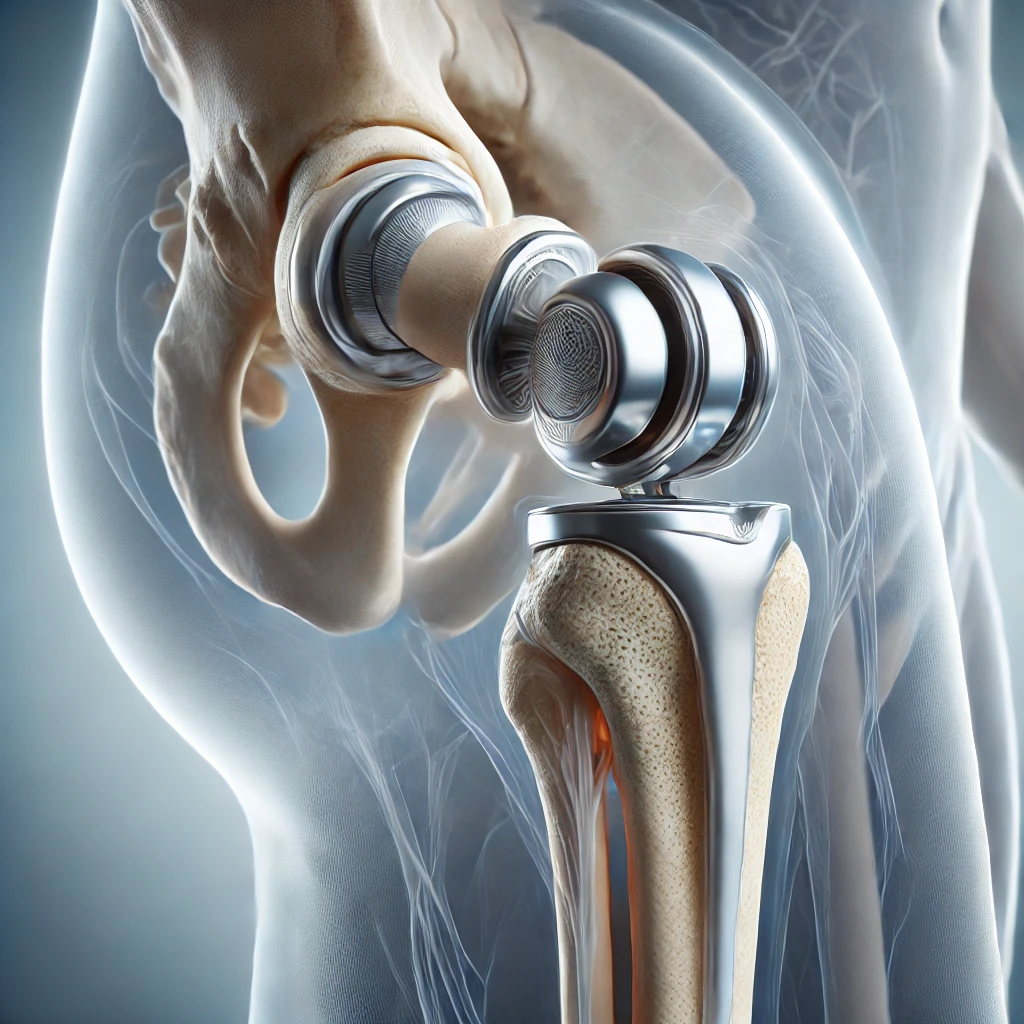

تعویض مفصل لگن

روش جراحی برای جایگزینی مفصل آسیب دیده با پروتز مصنوعی است که درد را کاهش داده و حرکت را بهبود می‌بخشد.